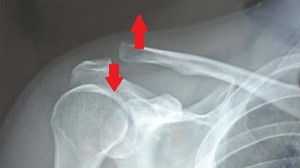

*肩鎖関節脱臼のレントゲン

(矢印の所で脱臼が起こっています)